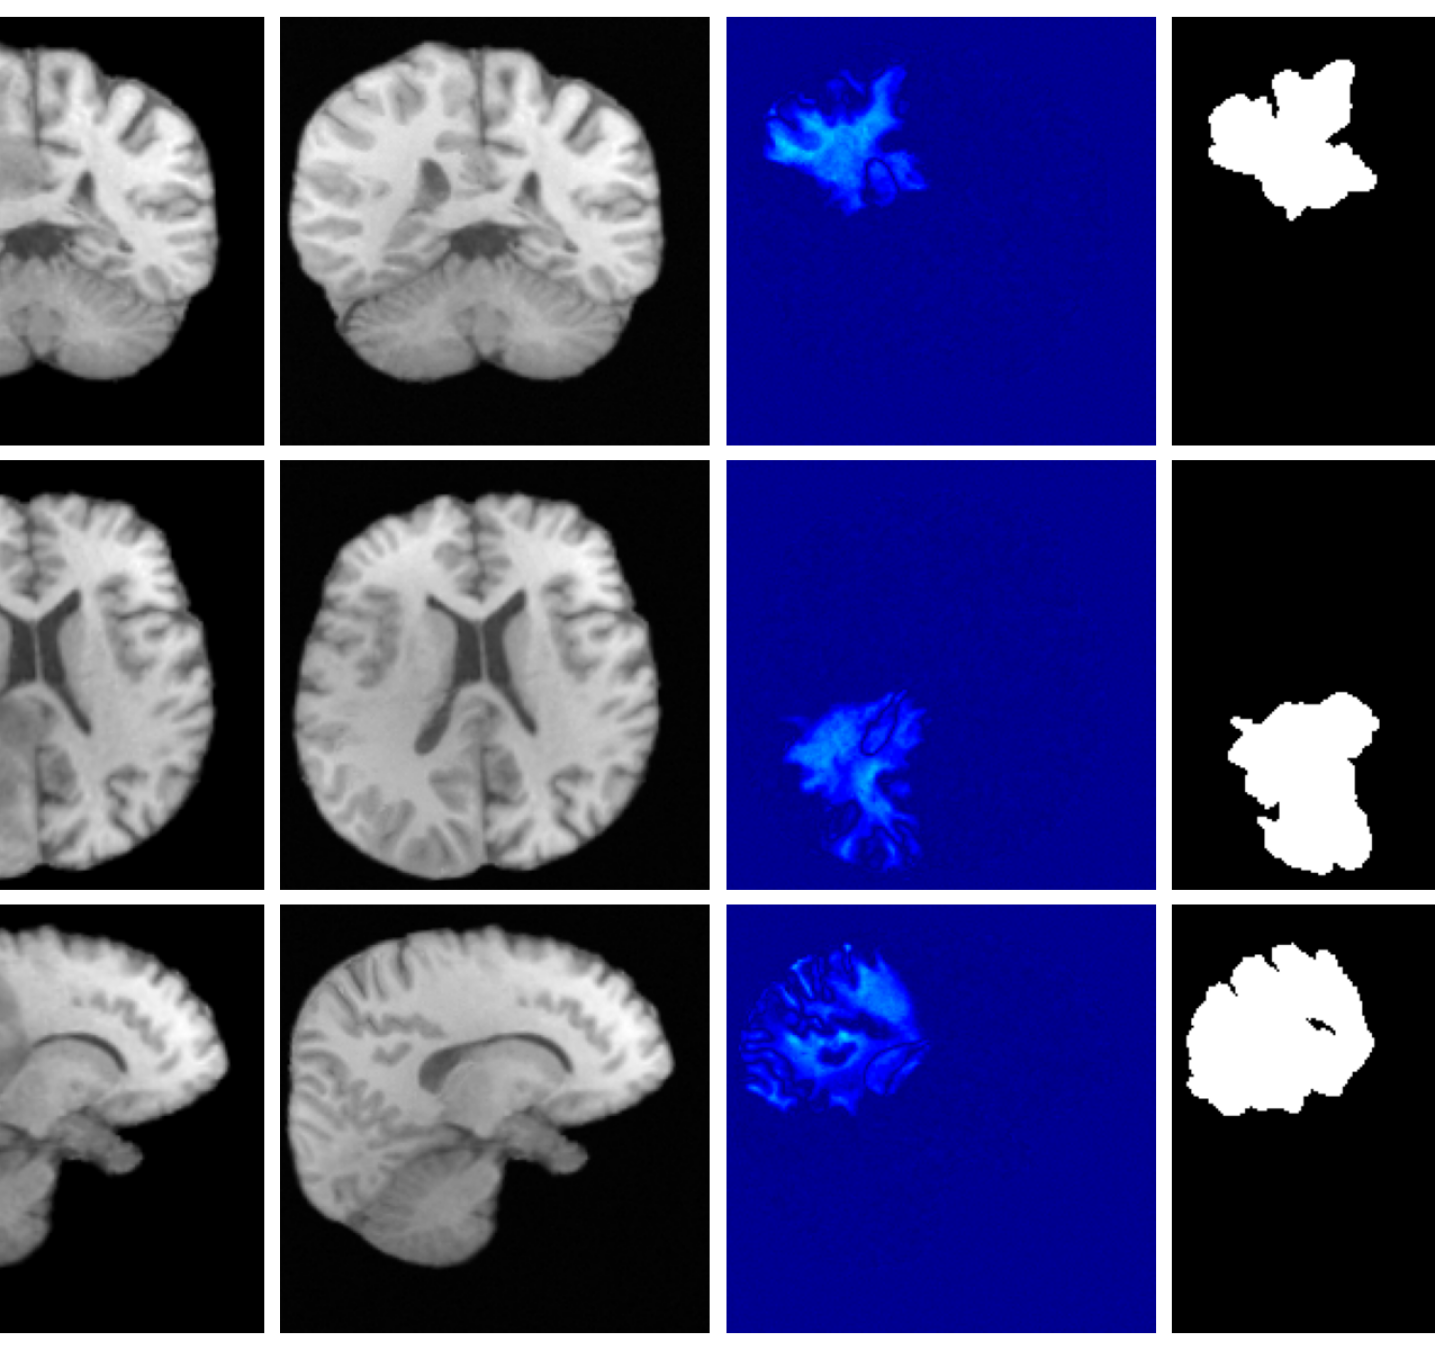

4.3 Image inpainting results

Inpainting results are given in Table 2. Our method achieves the best overall performance, attaining the highest rank on both datasets. For ATLAS, our method outperforms all baselines with improvements of 39.2% (VAE), 8.3% (VAE), 2.7% (VAE), 44.2% (LDM), 19.0% (LDM), and 51.4% (LDM). On BraTS, it improves over the best baselines by 25.6% (VAE), 5.2% (VAE), 27.4% (LDM), and 15.2% (LDM), while remaining competitive on the remaining metrics.

Figure 3 (additional examples in Appendix A.9) shows that SynthSR preserves healthy tissue but struggles with large lesions, while DDPM-2D and DDPM-3D, despite producing high-contrast anomaly maps, generate unrealistic homogeneous inpainting, consistent with their lower performance in Table 2. In contrast, our method yields the most anatomically plausible inpainted regions, although anomaly maps appear subtle due to low contrast between lesions and healthy tissue.

A.9 Additional qualitative inpainting results

Additional qualitative results for the ATLAS and BraTS datasets are given in Figures 12 and 13, respectively.